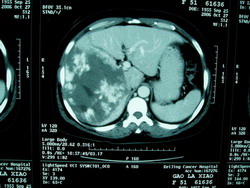

其它輔助檢查: 腹部平片顯示肝臟布滿鈣化區,類似結腸癌肝轉移。B超為回聲不均勻的多個結節;CT表現也多樣,呈多個低密度區伴周邊血管影中度增強,腫瘤內多個低血管點,有時小膽管擴張一些肝內門靜脈分支不顯影肝臟輪廓不變;血管造影顯示肝臟多個低血管腫塊